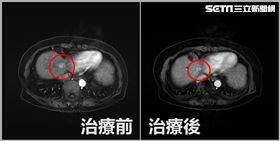

13年罹肝癌3次!75歲嬤一習慣腫瘤消失

肝癌位居國內十大癌症死因第二名,根據衛福部統計,11...

台中83歲廖奶奶7年前因吐血、腹水緊急就醫,當時肚子...

2024/07/30 10:18